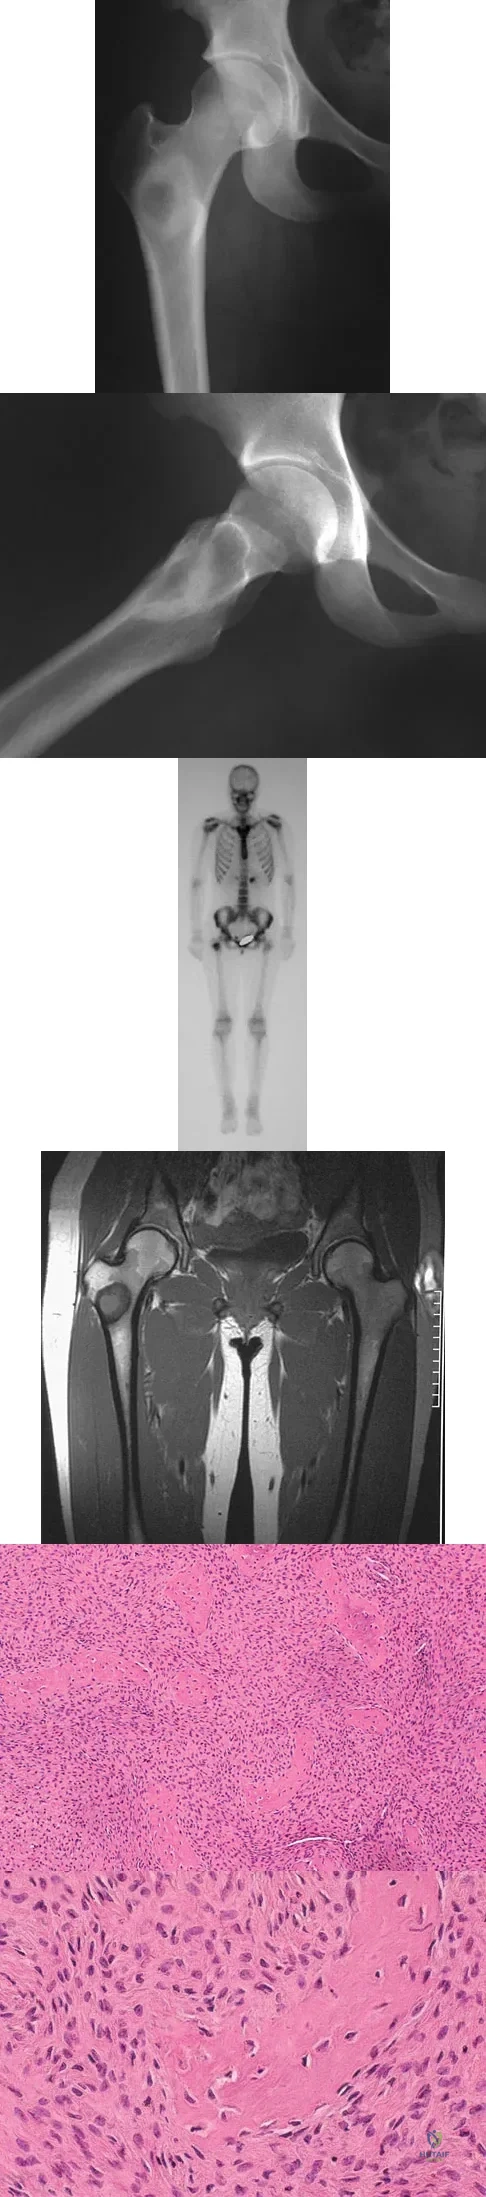

A 16-year-old girl injured her hip in a fall. Radiographs are shown in Figures 14a and 14b. She denies any history of pain prior to the fall and is currently asymptomatic. A bone scan, MRI scan, and biopsy specimens are shown in Figures 14c through 14f. What is the most likely diagnosis?

Explanation